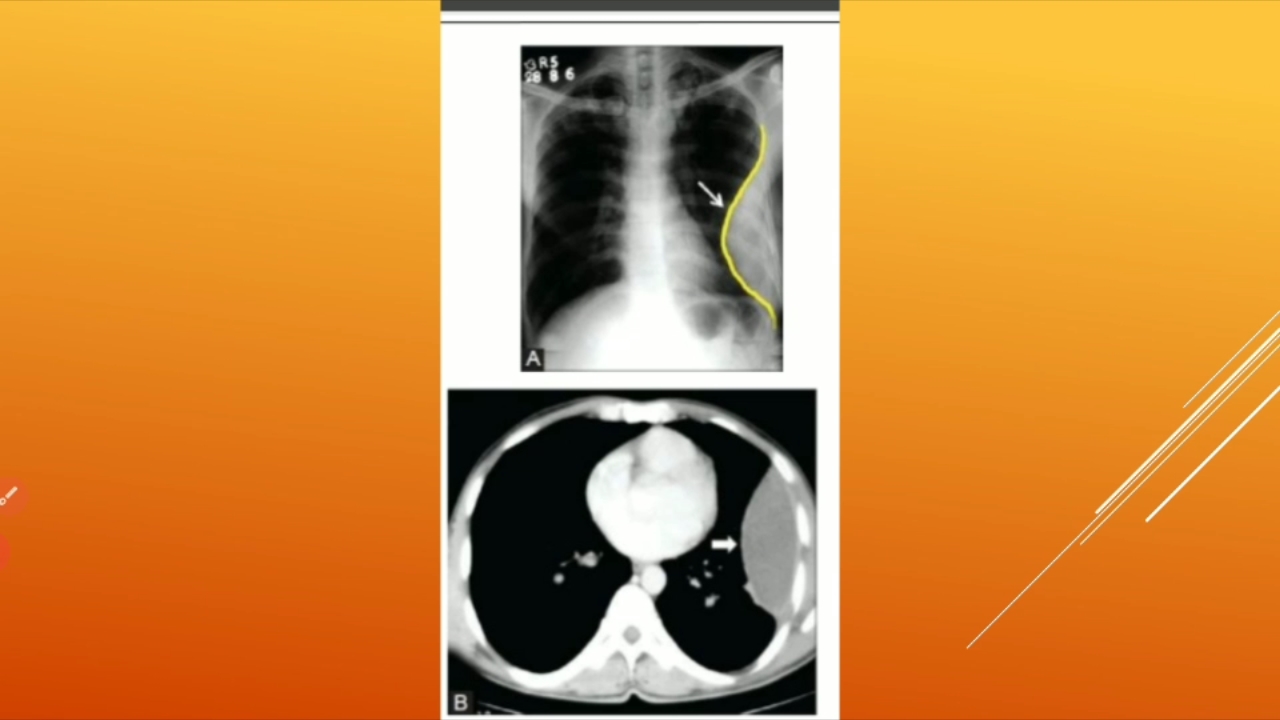

پخش صدا مقدمات بیماری های تنفس جلسه 8 اشتراکگذاری لیست پخش ۰ نظر ۰ نظر دانلود دانلود ویدیو دانلود کیفیت 720p ۱۸۳.۲۴ مگابایت دانلود کیفیت 480p ۱۱۶.۸۴ مگابایت دانلود کیفیت 360p ۸۳.۸۸ مگابایت دانلود کیفیت 240p ۵۵.۴۵ مگابایت دانلود کیفیت 144p ۳۸.۲۶ مگابایت گزارش تخلف بیشتر گزینههای بیشتر لیست پخش لایکها گزارش تخلف ۰ لایک Medical.kau98 منتشر شده در تاریخ ۱۴۰۰/۰۷/۲۶ این کانال دنبال شد دنبال کردهاید دنبال کردن این کانال دنبال کردن مقدمات بیماری های تنفس جلسه 8تاریخ1400.07.26 ادامه آموزش نظرات لبخند لبخند لغو ثبت نظری برای نمایش وجود ندارد.